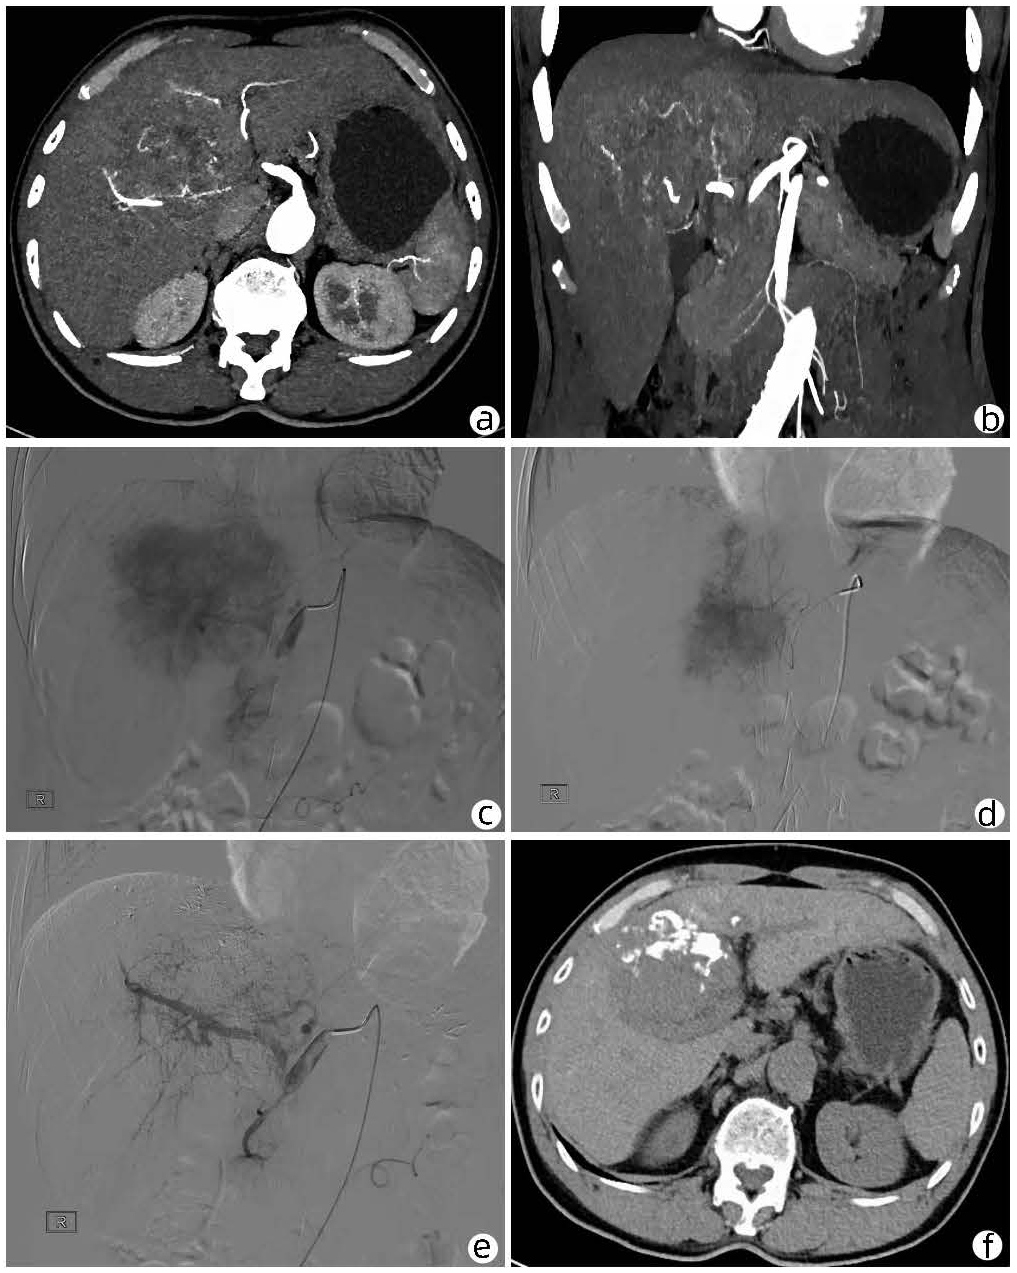

Local embolization combined with targeted comprehensive immunotherapy in treatment of sarcomatoid hepatocellular carcinoma: A case report

Jin LEI, Linzhi ZHANG, Yinying LU, Bowen CHEN, Shi ZUO

2022, 38(4): 880-882. DOI: 10.3969/j.issn.1001-5256.2022.04.026

Abstract(1227) HTML (425) PDF (3487KB)(61)

Abstract: